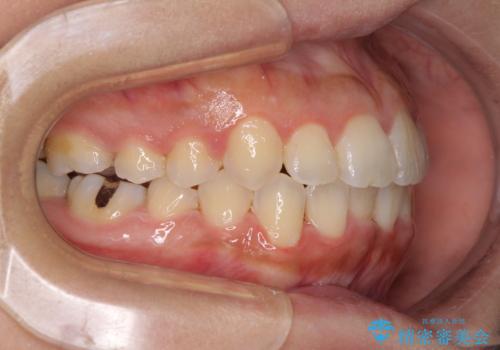

前歯のデコボコをインビザラインでスッキリと

- 上下前歯のデコボコを気にして来院された患者様です。

デコボコを解消する過程で、歯列の拡大により口元が突出する可能性があったため、4本の親知らずを抜歯しておき、歯列全体が後方に移動するように設計し、インビザラインにて矯正治療を行うこととしました。

日々の装着時間をしっかりと守って治療の臨んでくださったため、治療前のシミュレーションに近い形で矯正治療を進めて行くことができました。